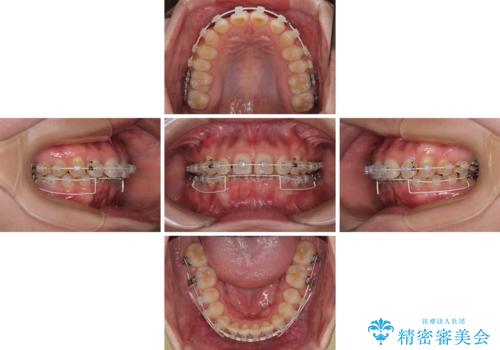

隠れた前歯が気になる ディープバイトのワイヤー矯正治療

- 下顎前歯が完全に隠れてしまっていることを気にして来院された患者様です。

下顎の臼歯が手前に傾斜していることで咬み合わせが深くなってしまい、下顎前歯が見えないほどに上顎前歯が覆い被さっている状態でした。

下顎臼歯を起き上がらせるためにユーティリティーアーチを使用し、一気に深い咬み合わせを改善することができました。